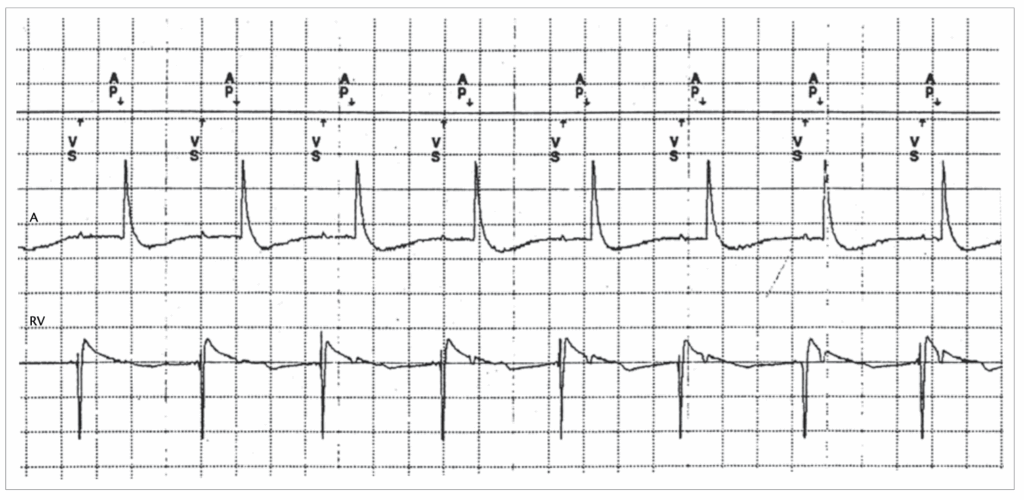

DDI

1 – There is loss of AV synchrony with atrial sensed events (AS) at a constant ventricular pacing (VP) rate 60 bpm (VP-VP 996 – 1000 ms) -> this excludes DDD and VDD.

2 – In DDI mode -> VA interval is triggered after a VP or VS events. AR that fall within the PVARP do not inhibit AP.

3 – AP occurs at the end of the VA interval (800 ms).

4 – AV synchrony is maintained after AP events.